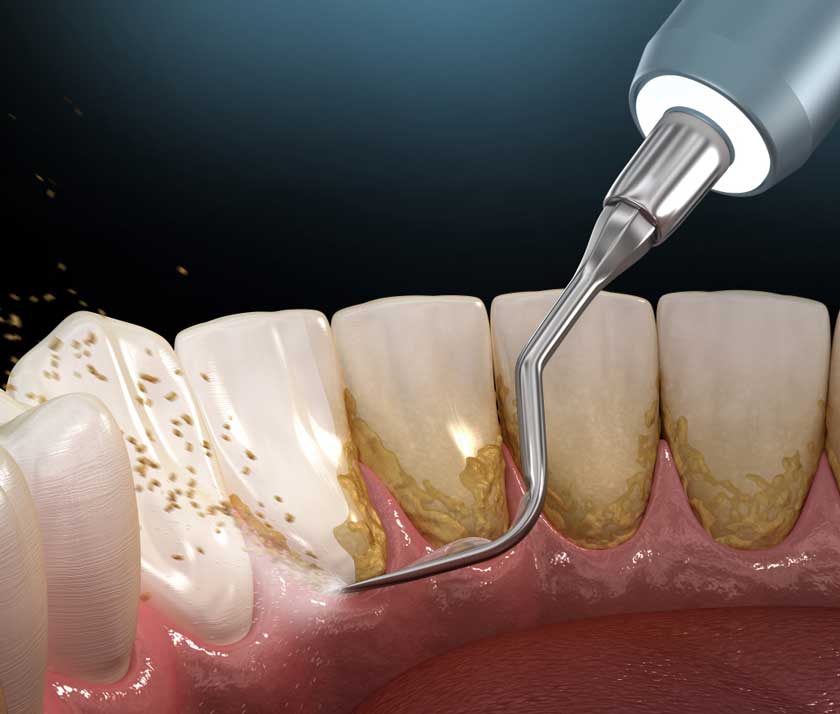

Nếu như mảng bám thức ăn thừa có thể làm sạch thông qua việc vệ sinh răng miệng hằng ngày thì vôi răng lại có độ cứng chắc cao, độ bám chặt nên không thể loại bỏ bằng bàn chải mà cần đến dụng cụ chuyên dụng và nha sĩ.

Cạo vôi răng định kỳ là cách chăm sóc răng miệng hiệu quả

Trong quá trình cạo vôi răng chuyên nghiệp, vôi răng sẽ được loại bỏ, vi khuẩn bị tiêu diệt và khoang miệng được vệ sinh chuyên sâu hơn. Nhờ đó, răng sẽ trở nên trắng sáng, hơn thở thơm tho, mang lại thẩm mỹ và sự tự tin khi giao tiếp.